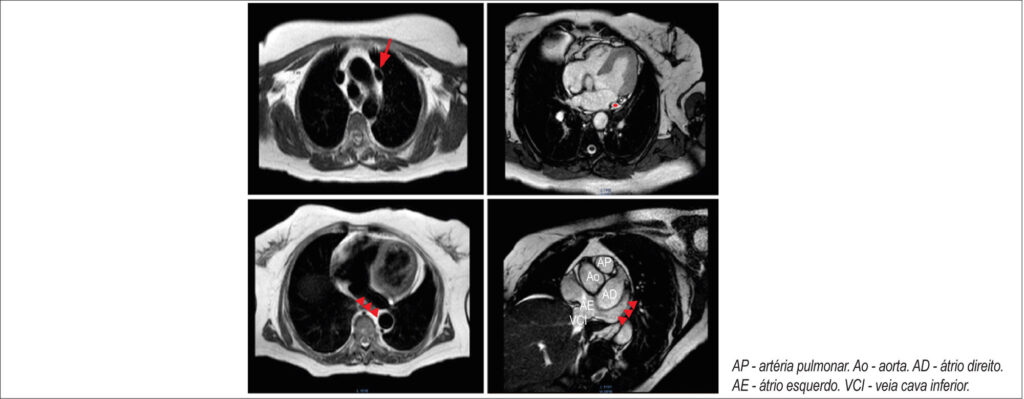

Mulher de 72 anos com hipertensão foi internada por parada cardíaca súbita secundária a fibrilação ventricular idiopática. Ressonância magnética cardíaca revelou uma veia cava superior esquerda persistente (VCSP) sem outras alterações cardiovasculares. Propôs-se o cardioversor-desfibrilador implantável (CDI) com acesso à esquerda. No intraoperatório, a canulação da veia cefálica inseriu o fio guia no VCSP que drenava no seio coronário e, posteriormente, no átrio direito. Com uma manobra de alça larga, posicionou-se a ponta do eletrodo voltada para a valva tricúspide e o acesso ao ventrículo direito foi obtido com o posicionamento do eletrodo ventricular. Os parâmetros do dispositivo foram verificados e estavam adequados, e o procedimento finalizado com fixação ativa, tempo de fluoroscopia de 1,35 minutos e dose de radiação de 143,12 µGy/cm2. Foram observados parâmetros de estimulação normais no seguimento de 3 anos.

A VCSP é uma anomalia venosa congênita, presente em 0,5% da população geral, geralmente assintomática e inerente em procedimentos invasivos ou de imagem. Embora não seja uma contraindicação para o CDI, a colocação do eletrodo é desafiadora, pois precisa contornar duas dobras, uma no seio coronário e outra na valva tricúspide. A implantação com técnicas de modelagem de estilete ou de alça larga é confiável e apresenta bom resultado, e os parâmetros de estimulação no seguimento de longo prazo não são afetados.